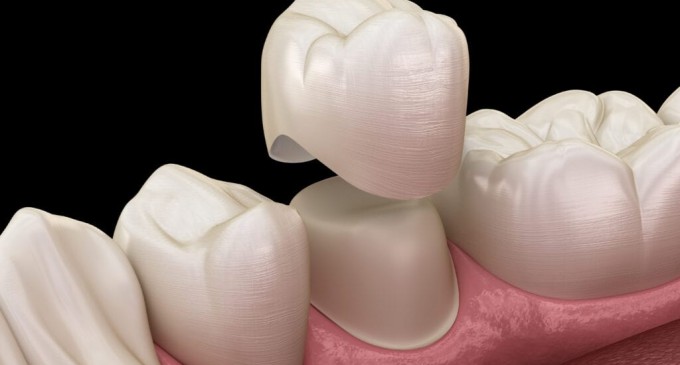

Coroanele moderne pot fi realizate din zirconiu, ceramică integrală, ceramică metalică, aur, ceramică vitroasă, porțelan și alte materiale. Aliajele metalice servesc drept cadru pentru produs, după care sunt acoperite cu ceramică.

Când se utilizează ceramică fără metal pentru coroane dentare, produsele pot avea o structură solidă sau pot conține dioxid de zirconiu, care servește drept cadru. Unele materiale sunt învechite și din cauza numărului mare de manifestări negative nu sunt folosite.